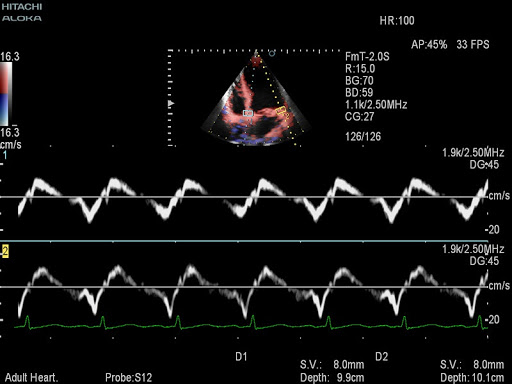

- Dual Doppler - двойной допплер (два одновременных контрольных объёма в режимах PW и TDI)

Dual Doppler - двойной допплер (два одновременных контрольных объёма в режимах PW и TDI)